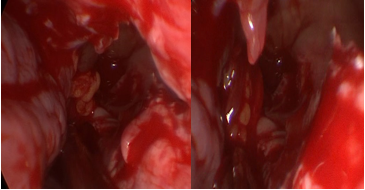

Surgical treatment was indicated. By an endonasal approach with endoscopes, the mucosa and medial capsule of the tumor were resected aspirating myxoid content (Figure 3).

Figure 3 Endonasal view with endoscopes.

A: aspiration through a middle antrostomy of myxoid material, B: middle mega-antrostomy after marsupialization and resection of a sector of the mucocele capsule for histopathological study. The arrow indicates the middle extrusion of the orbital fat.

When we did the marsupialization of the mucocele, at the roof of the maxillary sinus level, an extrusion of orbital fat and bleeding from the infraorbital artery occurred. By using bipolar coagulation, the bleeding could be resolved.